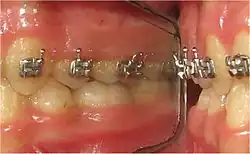

- Interpositions linguales : depuis la percée de la gencive, les dents définitives poursuivent une éruption passive jusqu'à toute occlusion (contact). Quelle occlusion ? Non celle avec la dent antagoniste (déglutition physiologique), mais bien celle des 1500 à 2000 pressions verticales quotidiennes de la langue sur les arcades dentaires. Il s'ensuit un ralentissement, suivi d'un arrêt prématuré de l'éruption de la dent définitive (Fig.1 et 2).

Les interpositions linguales induisent l'arrêt prématuré de l'éruption passive des dents dans la cavité buccale. L'interception consiste à créer le contact dento-dentaire antagoniste par réduction brutale d'un Espace libre trop grand. Ce contact entre des dents antagonsite stimule les mécanorécepteurs de la proprioception desmodontale (sensibilité tactile inconsciente[16],[17],[46],[47]).

- 2. Stimulera les mécanorécepteurs périodontaux lors de l'intercuspidation maximale (Fig. 18) des 1500 à 2000 déglutition salivaire quotidiennes (« occlusion réflexe » et déglutition physiologique « en dents serrées ») ;

- Dès le plus jeune âge (enfant, adolescent), mise en place d'un réducteur d'espace interocclusal de repos, ou REIOR[45], sur les molaires supérieures (Fig.13), gauche et droite : deux molaires lactéales (4 à 8 ans) ou deux molaires permanentes (à partir de 10 ans).

- Toutes les dents permanentes, « libres d'un REIOR », se retrouvent « suspendues dans le vide » : elles reprennent une éruption dento-alvéolaire passive. Ceci confirme le ralentissement et l'arrêt du processus d'éruption buccale par les pressions verticales de la langue lors de ses 1500 à 2000 interpositions quotidiennes entre les arcades dentaires (déglutition infantile, déglutition atypique).